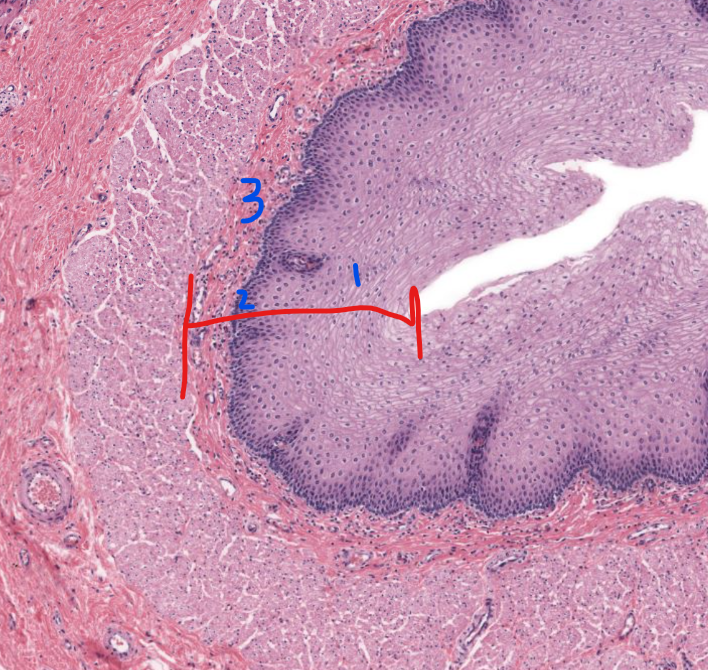

esophagus

note strat sq. epi

layer

mucosa of esophagus

strat.squamous n-keratineized epi

lamina propria

muscular mucosae

1

stratified squamous non-keratinized epithelium of esophagus

2

lamina propria of esophagus

3

muscularis mucosa of the esophagus